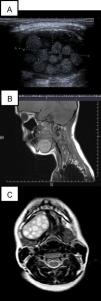

En la ecografía se apreció en la zona anatómica de la glándula submaxilar derecha, una tumoración quística de bordes bien definidos de 4,5×2,5cm con innumerables imágenes esféricas ecogénicas de entre 5–10mm de diámetro. No se observaron calcificaciones (fig. 1A). En la resonancia magnética de la zona se observó una imagen ovoidea de 4,2cm de eje mayor, de contornos bien definidos, en región lateral derecha del suelo de la boca (fig. 1B y C).

A) Ecografía: objetiva lesión heterogénea, de aspecto quístico, con múltiples estructuras redondeadas y ecogénicas en el interior. B) RM potenciada en T1. Plano parasagital derecho. Lesión en suelo de la boca, desplazando inferiormente el vientre anterior del músculo digástrico. C) RM potenciada en T2. Plano axial a nivel del suelo de la boca. Muestra lesión ovoidea, heterogénea, con múltiples áreas redondeadas en el interior hiperintensas. Desplaza medialmente el vientre muscular del geniogloso y comprime la glándula submandibular ipsilateral, situada posteriormente.